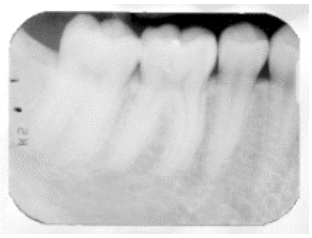

Embora o processamento do filme possa produzir

radiografias de excelentes qualidades, a falta de atenção

a detalhes pode acarretar muitos problemas e imagens

que não são radiograficamente ideais. Radiografias de má

qualidade contribuem para a perda de informação para o

diagnóstico e perda de tempo do profissional e do paciente.

De acordo com o livro “Técnicas radiográficas aplicadas à

odontologia de White e Pharoah (2015), há uma lista de

causas comuns de erros radiográficos.

Analise a radiografia a seguir.

Não contribui para esse possível erro radiográfico: